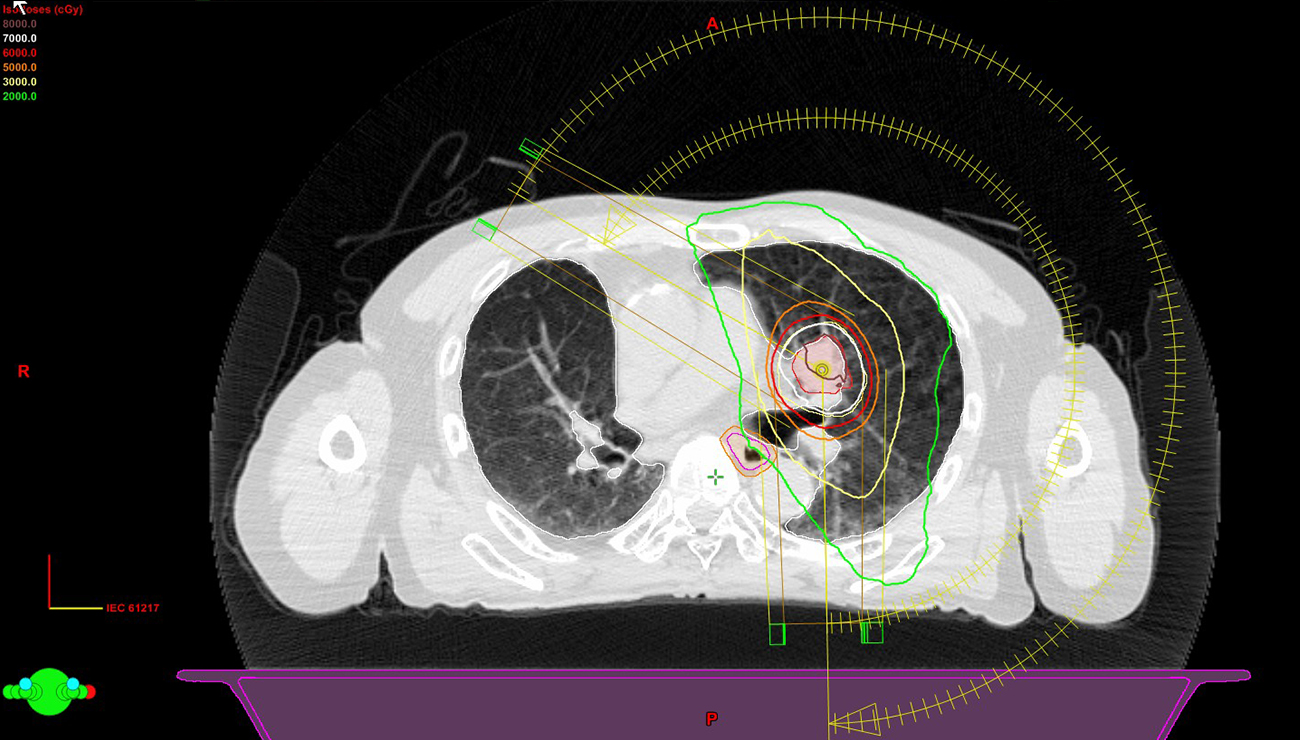

Stereotactic body radiotherapy using volumetric modulated arc therapy delivery

上述の照射技術をすべて駆使して、一度に大量の放射線を腫瘍にピンポイントにあてる技術です。適応疾患では高い治療効果を望めます。わたしたちは線量集中性を格段に高める照射法を提唱し、多くの 実績 を積んできました。 体幹部定位放射線治療に関して、YouTube 2018年12月市民公開講座「がんのピンポイント放射線治療の最先端」 でも解説しています。

左のグラフは一般的な方法(紫色点線)と当院の方法(赤色実線)とで、がん、治療範囲、周囲の正常臓器にかかる放射線量を示しています。 一般的な方法は、がんを含めた治療範囲に均一に放射線をあてるコンセプトを採用しています。一方で、当院が考案した方法3)は、周囲の正常臓器にかかる放射線量は一般的な方法と同程度に抑えつつ、がんを中心にした治療範囲には非常に高い放射線量を照射することが可能です。

(左上)左肺に発生した肺がん、(中央上)一般的な方法, 48Gy/4回 アイソセンター処方

(右上)当院の方法, 50Gy/5回 60%辺縁処方,

図は同じ早期肺がん患者さんに対して2種類の照射技術/考え方で体幹部定位放射線治療を行った場合の体の中の放射線量の分布(20グレイ1<青>~80グレイ<赤>)をグラデーションで表しています。正常肺・がんにかかる放射線量は施設で差があることが見て取れます。

図は同じ早期肺がん患者さんに対して2種類の照射技術/考え方で体幹部定位放射線治療を行った場合の体の中の放射線量の分布を示しています。正常肺・がんにかかる放射線量は施設で差があることが見て取れます。